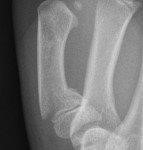

Imaging

- Request a finger X-ray if the injury is localised to one digit. This should have PA, oblique, and lateral views and include the metacarpal and carpometacarpal joint.

- A hand X-ray should have PA, oblique, and fan lateral views and will include all bones of the hand, carpus, and distal radio-ulnar joint.

Other phalangeal fractures

Undisplaced extra-articular fractures with NO rotational deformity

- Buddy strap and resting volar slab with follow up in Plastic Surgery clinic in 1-2 days.

Displaced, angulated, intra-articular fractures or rotational deformity

- Reduce fracture under ring block +/- sedation if appropriate. Otherwise refer to the Plastic Surgery team.

Metacarpal fractures (2nd to 5th)

- Resting volar slab and follow up with Plastic Surgery clinic in 1-2 days.

- Most common is 5th "Boxer's Fracture".

- Reduce fracture under nerve block +/- sedation if appropriate. Otherwise refer to Plastic Surgery team.